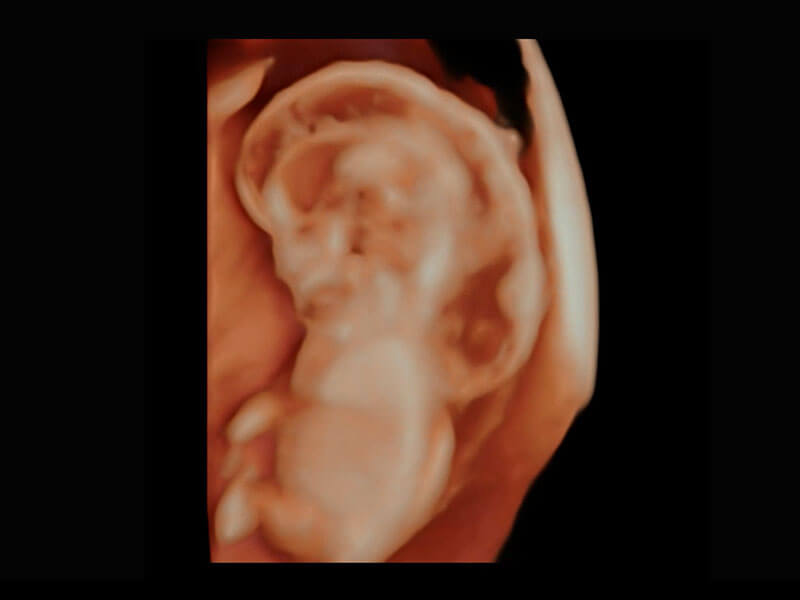

中晚孕筛查

P60提供简单易学易用的高端诊断工具,为您中晚孕筛查提供快速清晰的解剖信息。

1 OFD(HC): 87.03 mm

HC: 251.00 mm

GA: 27w 1d

HC/AC: 96.13 %

2 BPD: 70.56 mm

GA: 28 w 2d

S-Fetus(acq.)

& S-Fetus(meas.)

S-Fetus

S-Fetus能够助您在实时扫查过程中自动识别标准切面、自动测量并录入报告。一个按键,即可快速、高效地获取胎儿生理指标,简化您的产科检查操作。